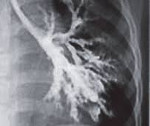

• Радиационная диагностика. Грубое усиление и деформация легочной модели, буллезная эмфизема выявлены при обзорной рентгенографии ОГК. КТ легких показывает общий бронхоэктаз. При кинематографической бронхографии их расширение и спад (воздушный шар) можно наблюдать во время акта дыхания.